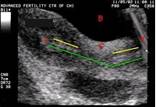

На рисунке 1 представлена УЗ-картина стимулированного яичника с множеством фолликулов. Красными точками помечен максимальный фолликул диаметром 18 мм:

Сколько же фолликулов необходимо для того, чтобы возможно было провести ЭКО?

Некоторые специалисты считают, что в процессе стимуляции необходимо получить как минимум 5 фолликулов размерами 14 мм. и более, однако противники этой теории утверждают, что возможно проведение процедуры уже при наличии хотя бы одного фолликула достаточного размера.

В большинстве клиник США придерживаются мнения о том, что необходимо как минимум 3-4 доминантных фолликула для того, чтобы процедура можно было считать успешной.